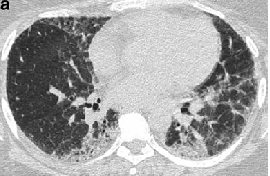

程大叔的胸部CT

治疗前